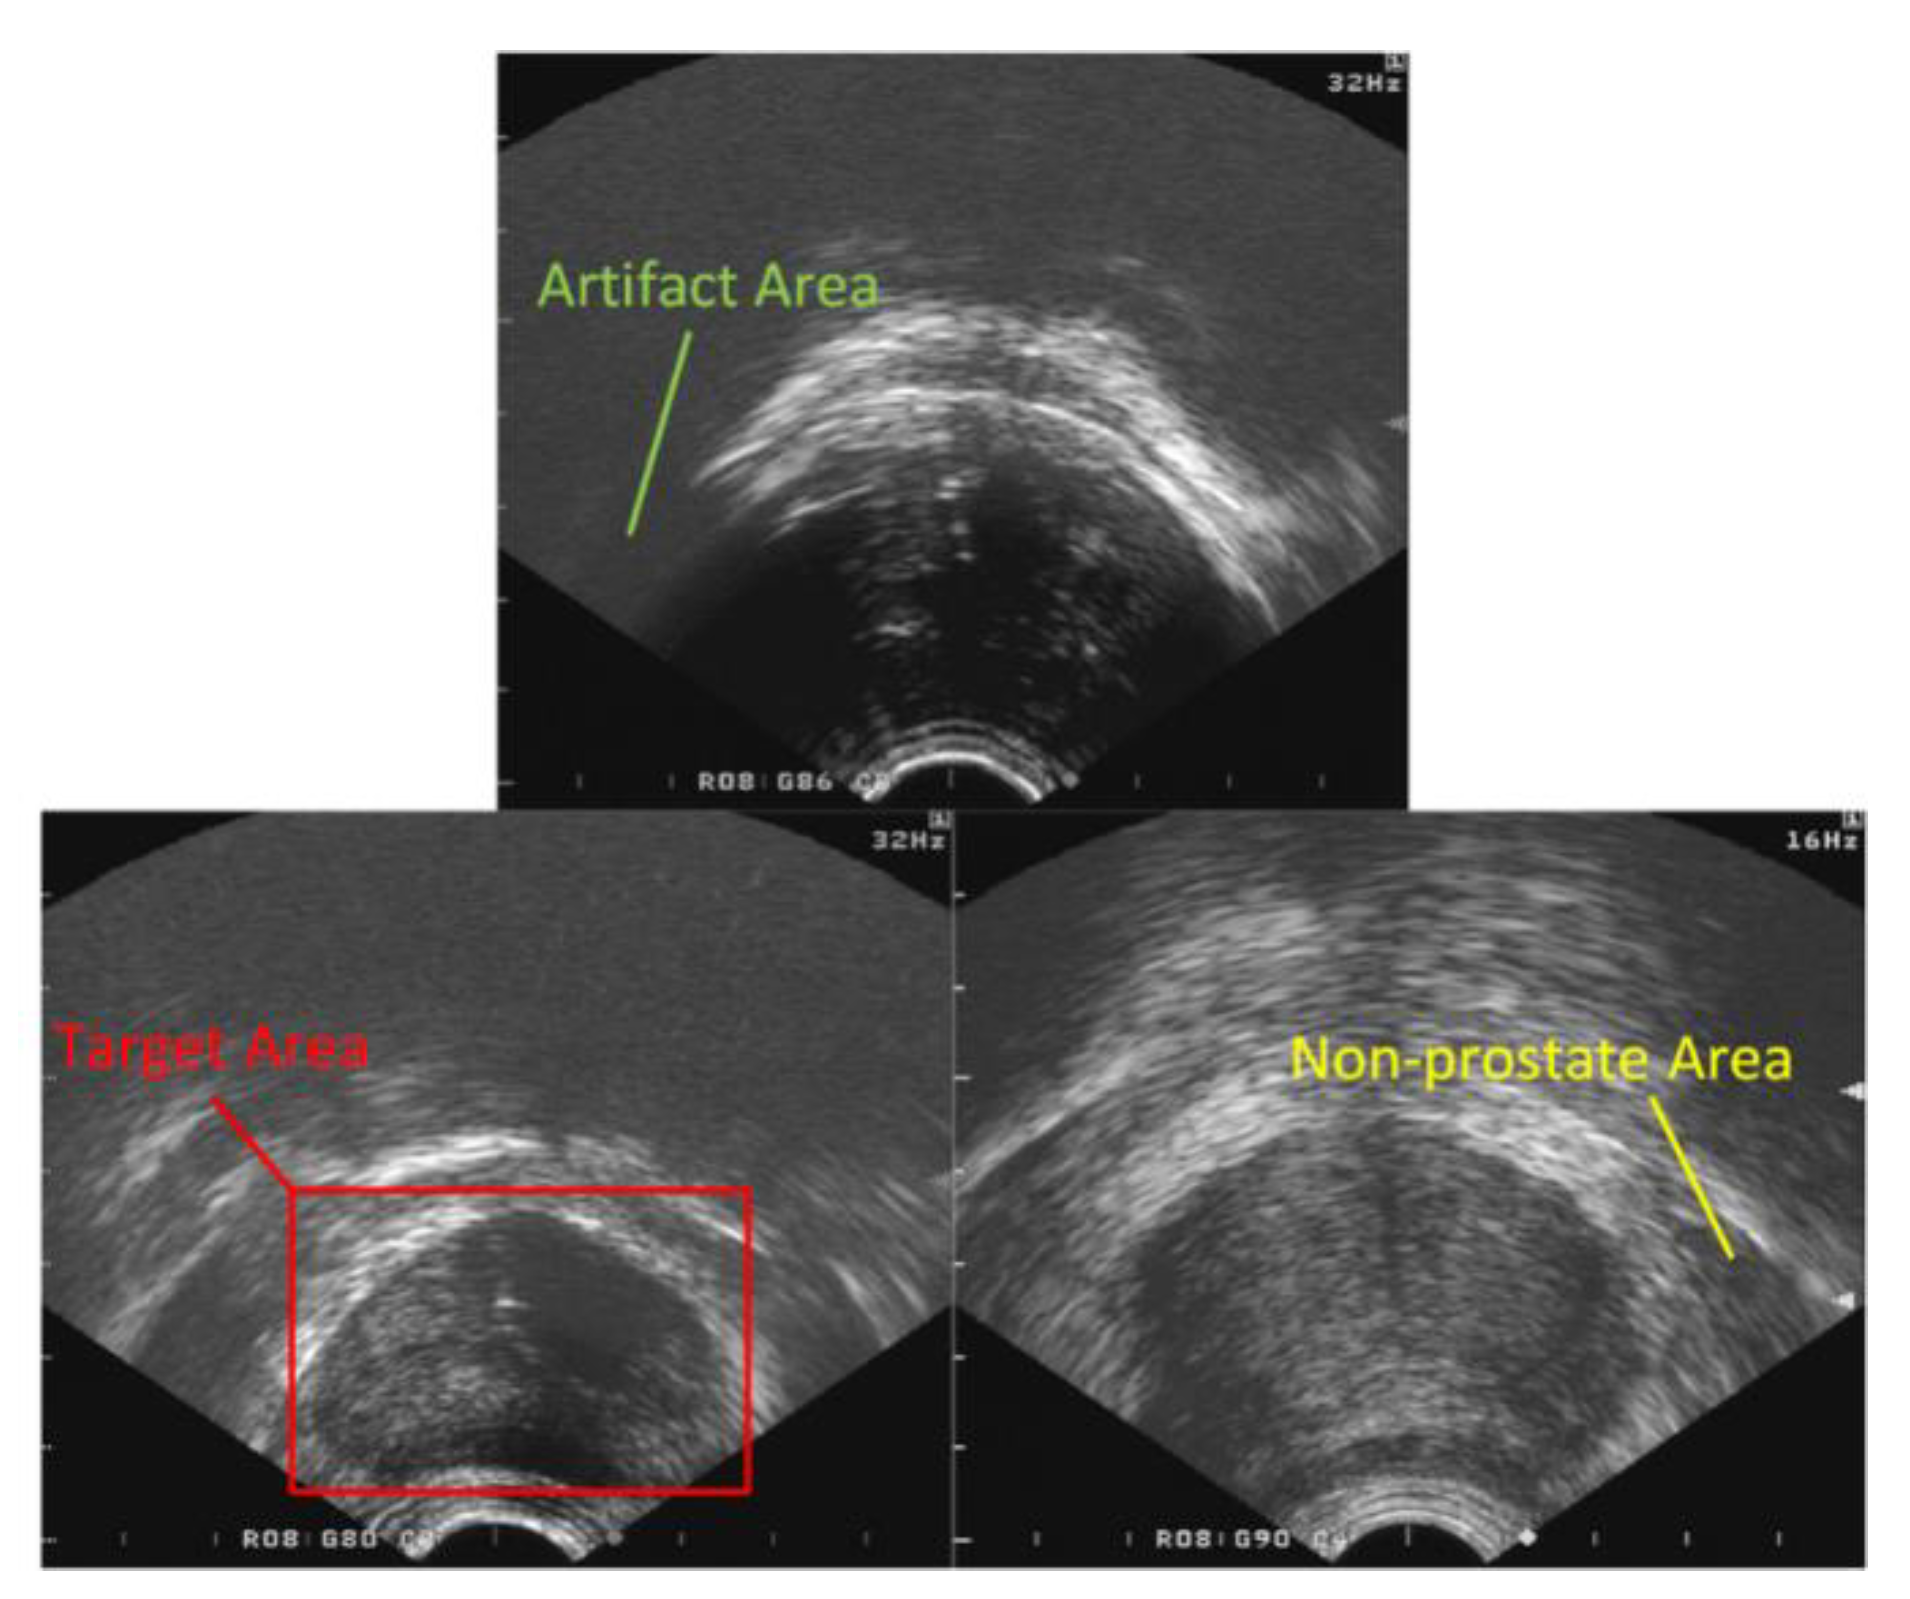

2.2. Target Area Screening Module

2.3. Target Area Screening Module